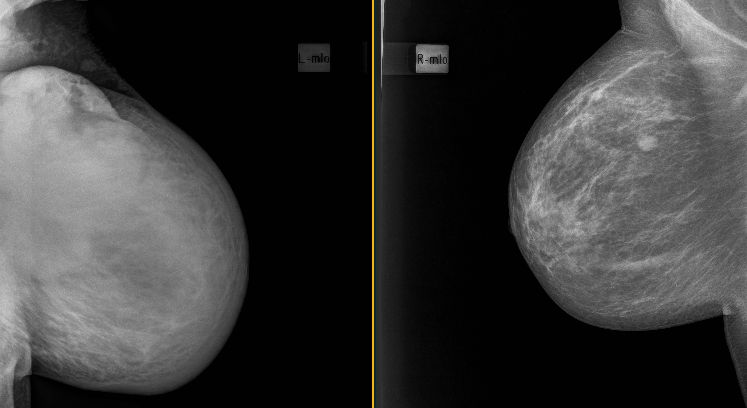

![]() 136mm großes multizentrisches Mammakarzinom links mit Hautulzeration | ||